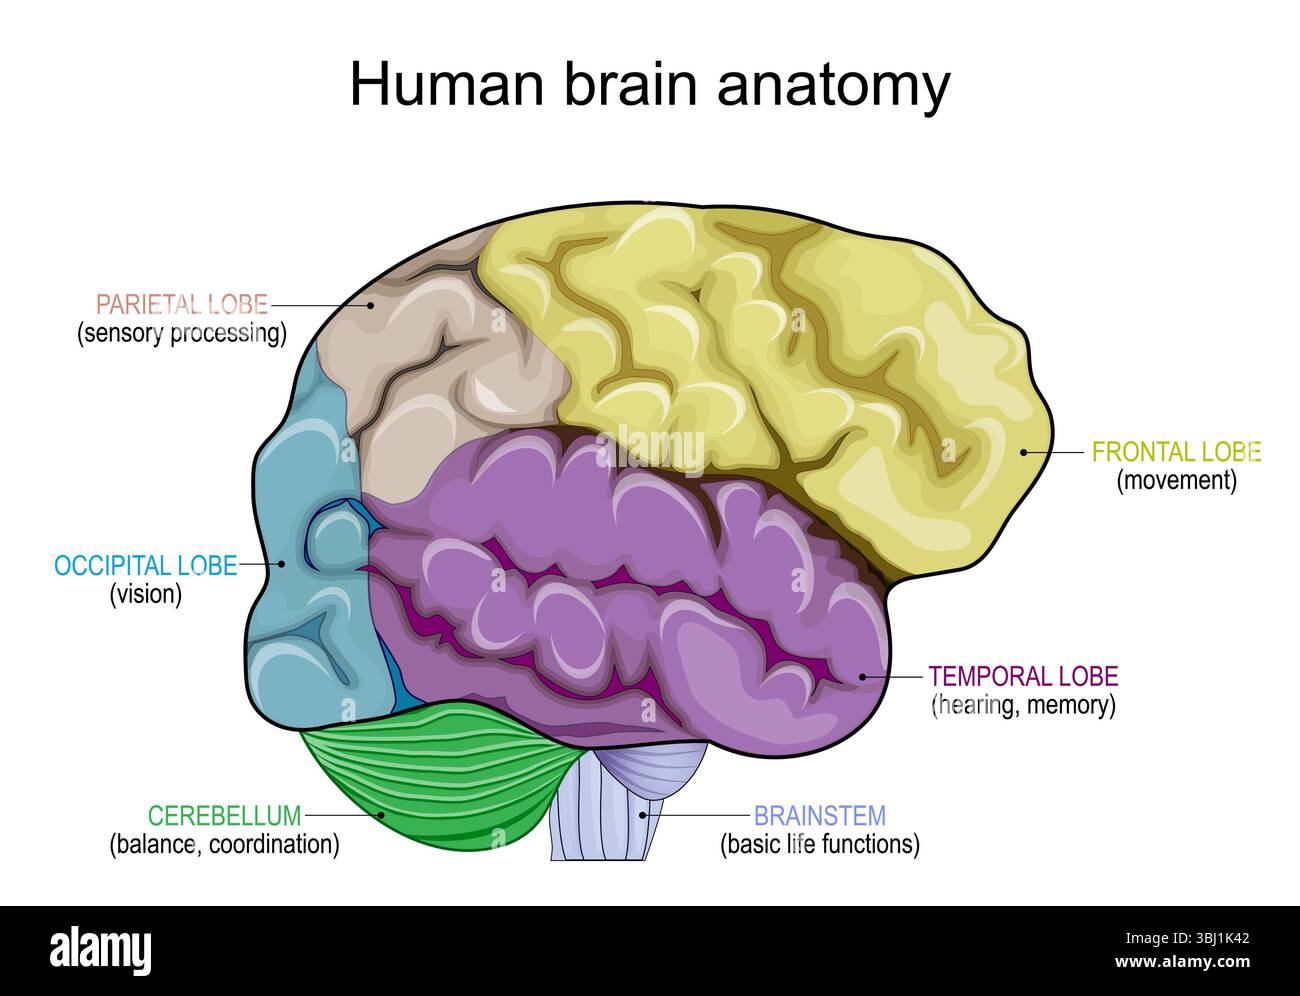

RF2Y8XEWG–Anatomia del cervello umano. Emisferi cerebrali, corteccia cerebrale, frontale, parietale, temporale, lobi occipitali, cervelletto e tronco cerebrale, fessura cerebrale.

RF3BJ1K42–Anatomia del cervello umano. Lobi frontali, occipitali, parietali e temporali, cervelletto e tronco cerebrale. Poster dettagliato del vettore

RF2R1KGAT–Struttura cerebrale umana. Emisferi e lobi della corteccia cerebrale. lobi frontali, temporali, occipitali e parietali. vista laterale e superiore